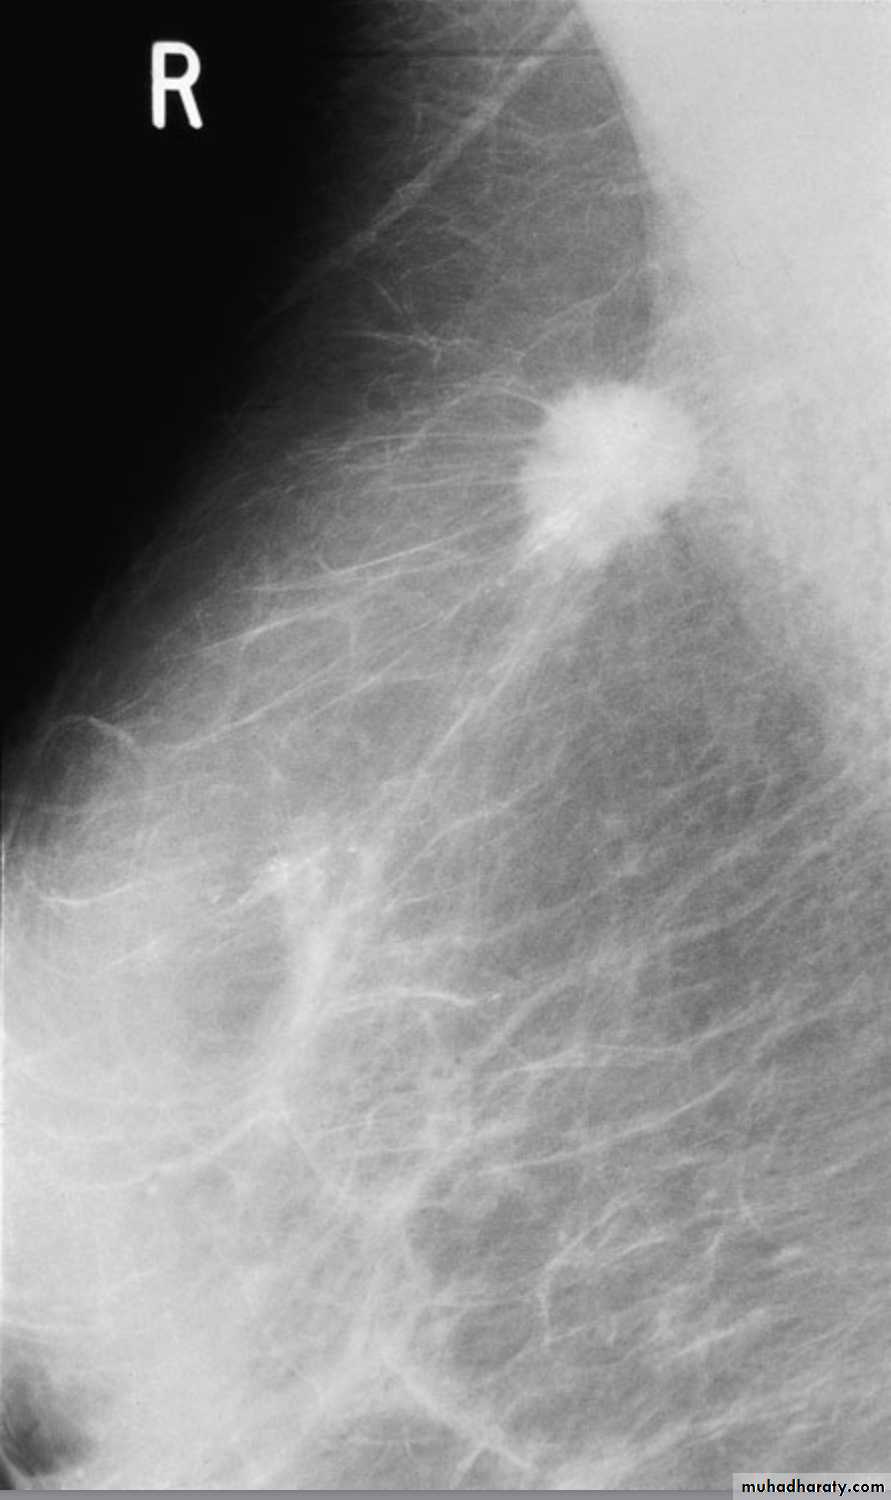

MammographySoft tissue X-rays are taken by placing the breast in direct contact with ultrasensitive film and exposing it to low-voltage, high-amperage X-rays.

The dose of radiation is approximately 0.1 Gy and therefore mammography is a very safe investigation.